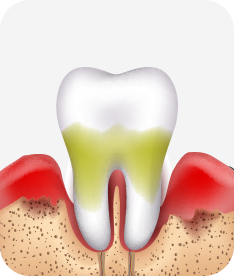

치주염 단계별 증상

치주염 (중기~말기)

주기적으로 잇몸이 붓고 피가 나며, 욱씬하거나 우리한 통증이 나타남.

치주치료 및 정도에 따라 치주수술(잇몸수술)이 필요함. 향후 관리 정도에 따라 3~6개월 간격으로 내원하여 유지치료를 시행하여야 함.

치주염 (말기)

잇몸이 항상 부어 있으며, 이가

흔들리는 정도가 점점 심해짐.

치주치료가 필요하며, 정도에 따라 치아를 발치하여야 할 수 있음.